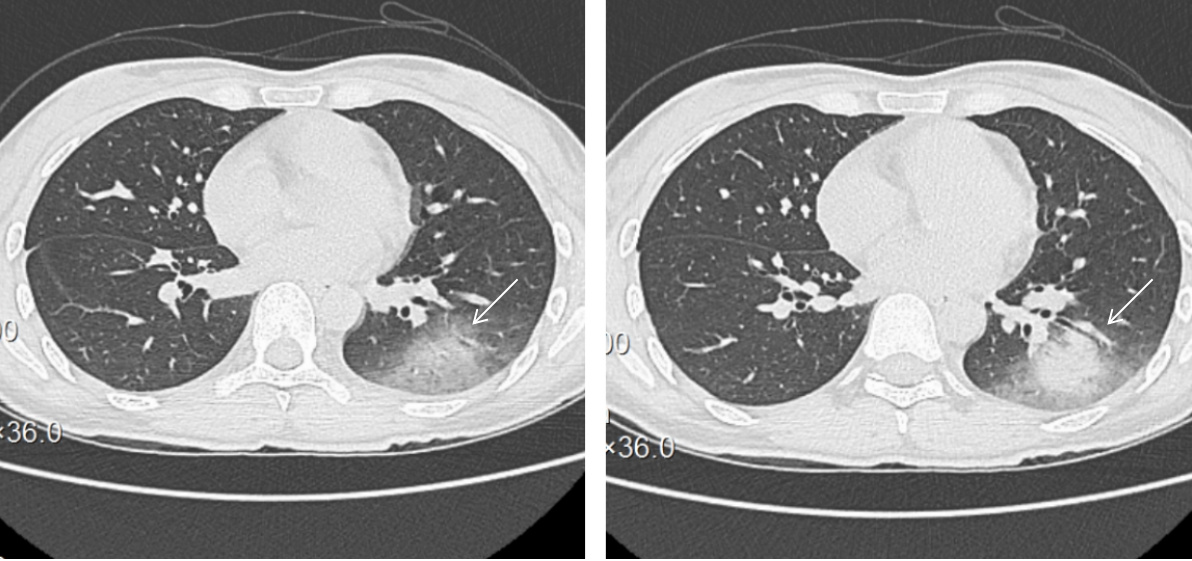

7月2日体温转正常,神志转清楚,但发现四肢肌力明显对称性减弱,医学研究委员会(MRC)总评分为0/60,上下肢肌张力稍微增高,全身感觉正常。复查腰椎穿刺检查,脑脊液压力135 mmH2O,脑脊液外观淡黄色,潘氏试验阳性,细胞计数63×106/L,单个核细胞100.0%,葡萄糖3.61 mmol/L(同期末梢指尖血糖9.3 mmol/L),氯125.9 mmol/L,蛋白定量1 399 mg/L; 动态脑电图提示:重度异常动态脑电图(图 2); 肌电图提示:左右胫前肌、左腓肠肌内侧头、右第一骨间肌未见明显纤颤、正尖波,轻重收缩募集相减少; 神经传导速度测定:左右腓总神经运动传导仅见微小波动,左右正中神经、左右尺神经、右胫神F波出现率降低或未引出; 重复神经电刺激未见明显异常。脑脊髓MRI提示:双侧额叶、右侧脑室后角旁白质及脑干多发异常信号并脑膜、脊膜强化,脑膜脑炎可能(图 3)。血清和脑脊液样本分别送检基于组织底物的间接免疫荧光法筛查三项、副肿瘤综合征18项抗体、自身免疫性脑炎21项抗体、中枢神经脱髓鞘7项抗体均为阴性; 血清周围神经病30项抗体中抗GT1a抗体IgM强阳性。修正诊断为CPN肺炎并ADEM和GBS重叠,予人免疫球蛋白(20 g/d,共5 d)和甲基强的松龙(80 mg/d,共3 d),然后口服泼尼松剂量[1 mg/(kg·d)],缓慢减少。治疗过程中发现颜面部肌肉瘫痪,口咽、颈部和上肢无力表现更为突出,患者在神志清楚,气道呛咳反射和咳嗽峰流速正常情况下因无法吞咽并气道保护能力差,拔管失败2次,随着治疗延续及康复干预,吞咽功能改善,气管插管17 d后才成功拔除气管插管。

| MRI: 双侧额叶皮层下白质区、右侧脑室后角旁白质,T1WI呈等、稍低信号(A),T2WI(B、C)、T2flair呈高信号(D、E),DWI呈稍高信号(F、G); 脑干见多发斑点、斑片状异常信号, T1WI呈等、稍低信号(H),增强后未见强化(I),T2WI呈高信号(J); 增强扫描硬脑膜可见硬化(K、L) 图 3 颅脑脊髓 |